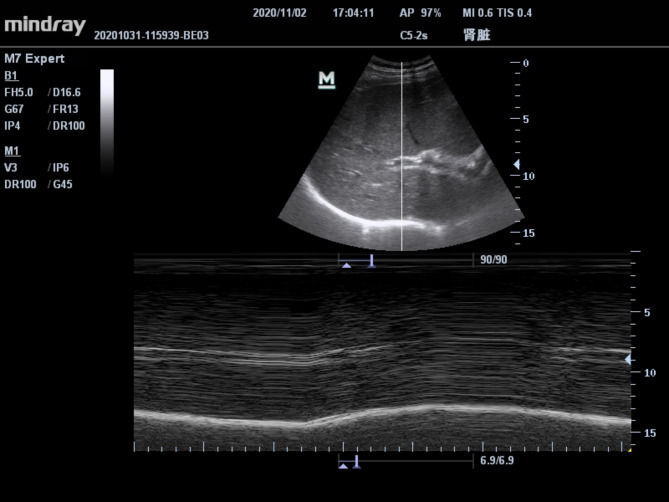

肩关节镜检查已成为一种常见的手术,但它往往与严重的术后疼痛有关。本研究旨在评价超声引导下喙突入路臂丛阻滞联合肩胛上后神经阻滞在肩关节镜下的镇痛效果。为此,将50例接受右肩关节镜检查的患者随机分为两组,每组25例。在全麻诱导前,两组患者接受不同程度的神经阻滞。在A组,参与者接受超声引导下锁骨上臂丛阻滞25 mL 0.3%罗哌卡因。B组在超声引导下行喙突入路臂丛神经阻滞和肩胛后上神经阻滞。阻滞前、阻滞后30 min采用m型超声测量膈肌运动,静息呼吸、深呼吸时记录膈肌麻痹情况。分别于术后1、6、12、24、48 h记录疼痛评分。同时记录PCA泵的实际按压次数和舒芬太尼的用量。共有45名患者完成了这项研究。镇静呼吸和深呼吸两种呼吸方式下,B组半膈肌麻痹发生率均显著低于A组。两组患者术后1、6、12、24、48小时疼痛评分相近。与锁骨上臂丛神经阻滞相比,喙突入路臂丛神经阻滞联合肩胛后上神经阻滞可显著减少半膈肌麻痹的发生,肩关节镜术后镇痛效果相当。因此,后者可能有利于不能忍受半膈肌麻痹的患者术后早期恢复。试验注册:本研究已于2021年4月2日在中国临床试验注册中心(ID ChiCTR2100043069)注册。

Shoulder arthroscopy has become a common procedure, but it is often associated with severe postoperative pain. This study aims to evaluate the analgesic effect of ultrasound-guided coracoid approach brachial plexus block combined with posterior suprascapular nerve block in shoulder arthroscopy. To this end, fifty patients undergoing right shoulder arthroscopy were randomly divided into two groups with 25 patients in each group. Before induction of general anesthesia, patients in the two groups received different nerve blocks. In Group A, participants received ultrasound-guided supraclavicular brachial plexus block with 25 mL 0.3% ropivacaine. In Group B, coracoid approach brachial plexus block and posterior suprascapular nerve block were carried out under ultrasound guidance. M-mode ultrasound was used to measure diaphragm movement before and 30 min after the block, and the presence of hemidiaphragm paralysis was recorded during calm breathing and deep breathing. Pain scores were recorded at 1, 6, 12, 24 and 48 h after surgery. The actual press times of the PCA pump and consumption of sufentanil were also recorded.A total of 45 patients completed this study. The incidence of hemidiaphragm paralysis in Group B was significantly lower than that in Group A under both calm breathing and deep breathing. The two groups displayed similar pain scores at 1, 6, 12, 24 and 48 h after surgery. Compared with supraclavicular brachial plexus block, coracoid approach brachial plexus block combined with posterior suprascapular nerve block can significantly reduce the occurrence of hemidiaphragm paralysis with an equivalent postoperative analgesic effect for shoulder arthroscopy. Therefore, the latter may be beneficial for early postoperative recovery in patients who cannot tolerate hemidiaphragm paralysis. Trial registration: This study was registered in the Chinese Clinical Trial Register (ID ChiCTR2100043069) on 04/02/2021.